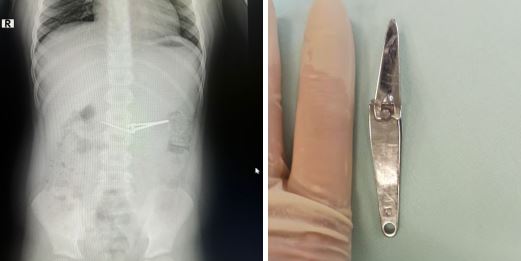

В Уфе врачи вытащили из желудка 6-летнего ребенка щипцы для стрижки ногтей